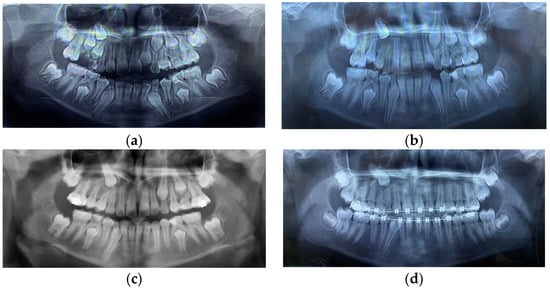

Figure 1.

(a) Initial panoramic X-ray showing the upper right canine in a very high position and transposition with the first premolar. (b,c) Different types of root DL affecting right premolars. No improvement regarding the position of the right canine after maxillary expansion. (d) The upper left second premolar also has a root DL.

After maxillary expansion, the first premolar partially erupted, but the second one was impacted due to the lack of space and both distally inclined and completely formed roots. The roots of the premolars had different types of DLs, from a slight flexion of the second premolar’s root to a true dilacerated root of the first premolar. The canine remained in the same position while the DC was still growing (Figure 1b).

To obtain more space for upper premolars and canines, the patient wore a low pull headgear to distalize the upper first molar and then fixed appliances to fulfil the objective of the orthodontic treatment. Because the canine did not change its position (Figure 1c), marsupialization of the cyst was tried, and consequently, the canine started to erupt between the roots of the first premolar. At this moment, it has been decided to incline the roots of the first premolar distally to prevent root resorption by the canine.

Regarding the cause–effect association between DC and root DL, in this case, DC could be the cause of root DL (taking into consideration the initial high and mesioinclined position of the canine, in transposition with the first premolar, along with its DC that had continued to grow, in closed contact with the apical half of the first premolar root, the DLs of first premolar root as the flexion of the second premolar root). This could be explained by the pressure applied by the cyst on that area of dense bone structure. The last panoramic X-ray (Figure 1d) showed a root DL of the second upper left premolar. Thus, the DL could have another cause, namely a genetic one, as a dental anomaly pattern (DAP) or associated dental anomaly (ADA), in which many dental anomalies coexist, as in this case, the canine impaction, transposition, DC, and root DL. The root DL of the impacted canine could also be seen on the CBCT (Figure 2a,b).